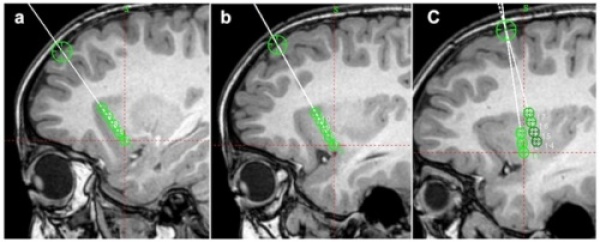

直径2mm、有効長4mmの凝固プローべを使用し、74℃、60秒間の温熱凝固を行うと、直径5mmの凝固病変が形成されることが経験的に知られています。そのため、5mm径の球体モデルを3次元的に組み合わせることで治療を計画します。Volume-based RFTCについてフランスの一施設から先行報告がありますが、本研究の新規性は先行研究よりもさらに小さなサイズの球体モデルを用いて治療を計画することで、より緻密で柔軟な治療を目指した点にあります(図2)。

図2:1回の熱凝固が5mm径の病変を形成すると想定し(緑の丸)、 それを組み合わせて治療を計画